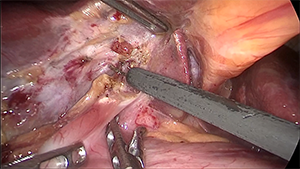

腹腔镜Ⅲb型肝门胆管癌根治术

作者:蔡翊 | 作者单位:湖南省人民医院

发布时间:2020-09-03 22:17:01